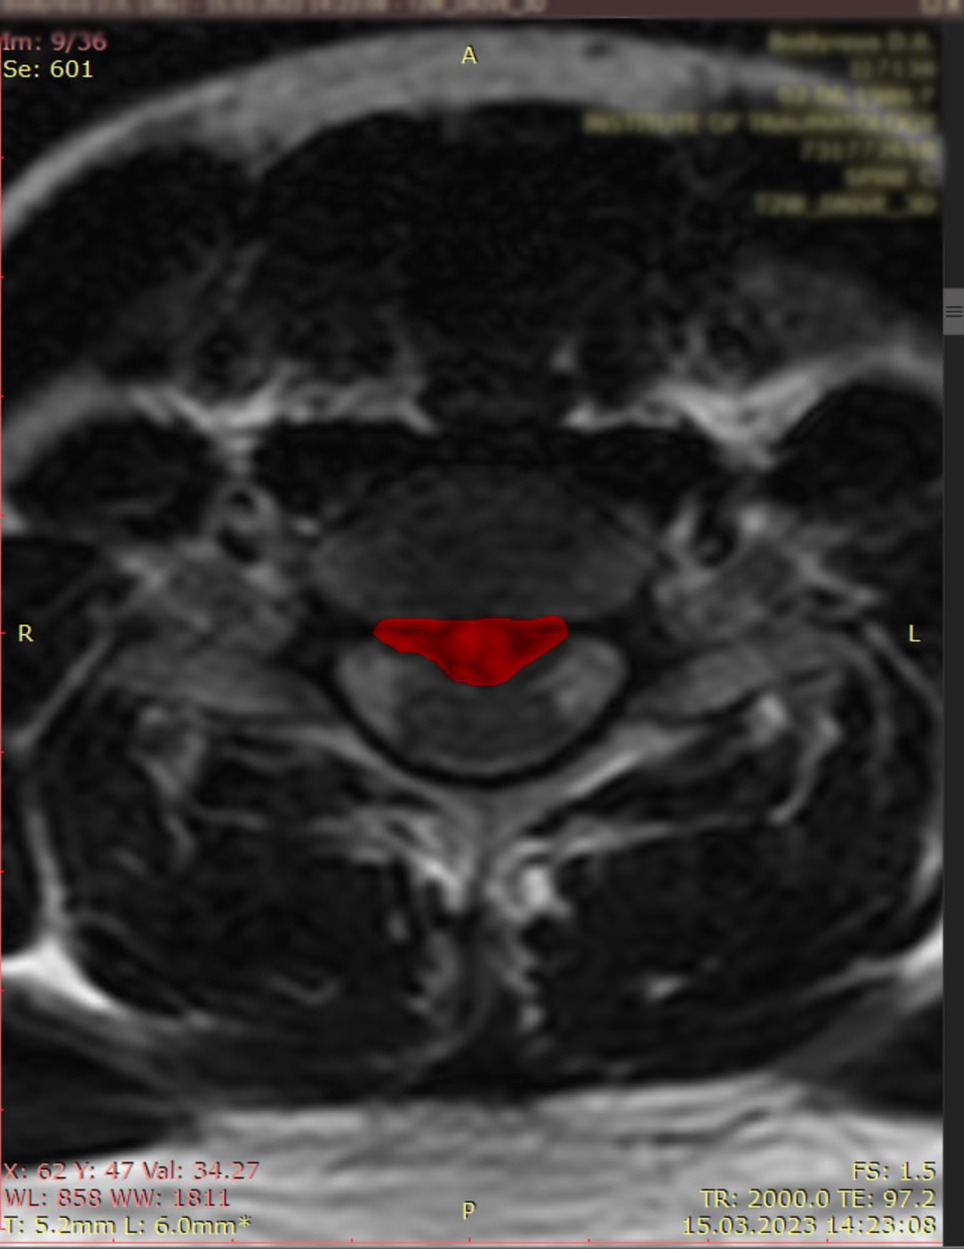

🔬 МРТ (магнітно-резонансна томографія) —

✅ "Золотий стандарт" у діагностиці грижі.